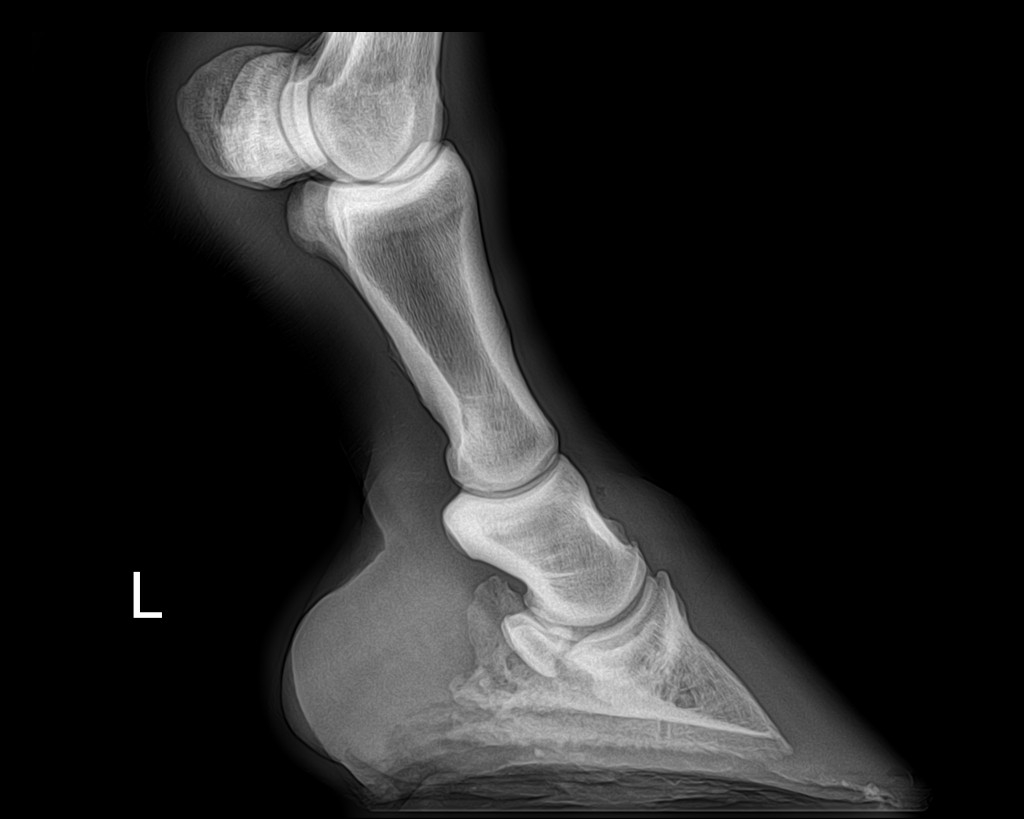

| Dire merci | juliie oui on aurait pu avoir pire, voici les derniers clichés radio du coup ( je sais qu'ils te font relativiser pour ton jaune ) AD ![]() ( On voit la petite pointe d'arthrose) AG ![]() (La on voit que la pointe d'arthrose est plus prononcée...Je sais si vous voyez, sinon j'entoure) Et là calcici...la calfifi...la Calcification ! ( Ça passe mieux sur un ton enjoué!) ![]() ![]() (Ce qui explique en grosse partie le côté trés sportif de ce journal ,heureusement qu'on bricole )erzebeth et takhan (mais je peux jamais t'identifier !!) Je vous prépare ça ( jsuis comme une folle ! J'adooooore les avants/aprés...sauf pr moi,là clairement ça va pas ds le bon sens ) |

| Dire merci | Oh punaise, la calcification fait pas rire ![]() Mais je prends volontiers ses sésamoïdes ![]() |